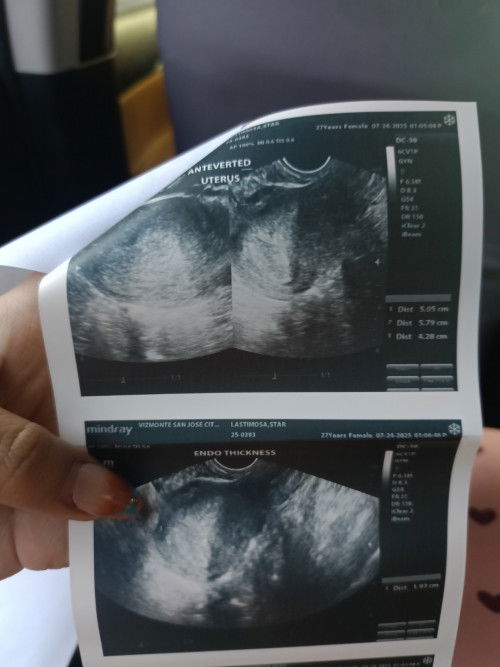

eto po

Ito pa